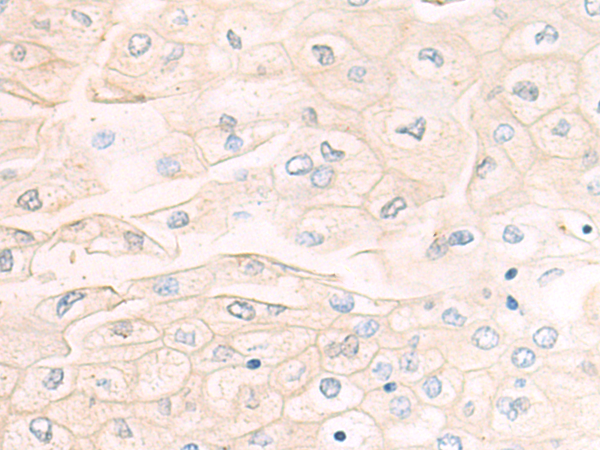

分类: 科研抗体货号: P05257别名: SCP2; SCP-2应用: IHC反应种属: Human, Mouse, Rat